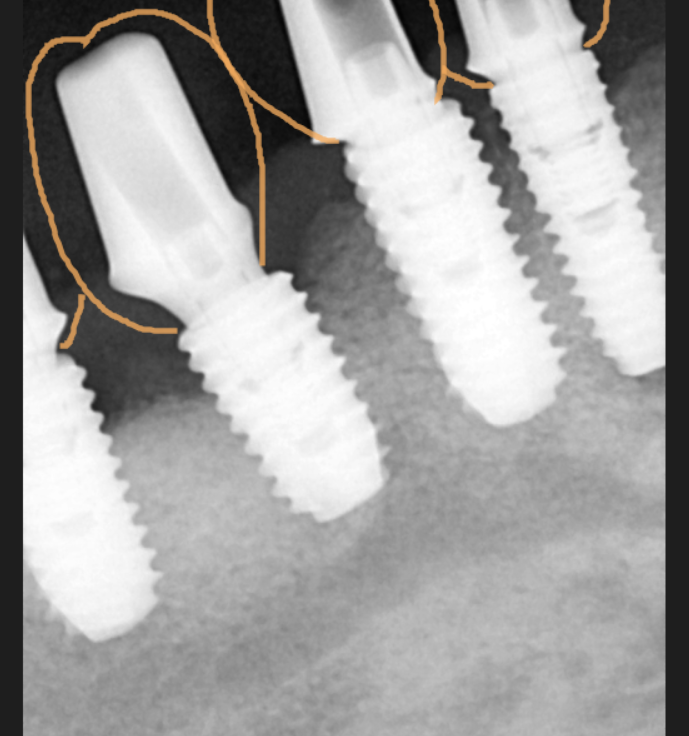

뼈가 많이 흡수되었는데요.

아래 임플란트는 문제 없었지만

윗니 어금니는 ct를 통해 남아있는 뼈를

분석하였습니다.

미리 네비게이션 기술을 활용하여

수술 식립 각도, 사이즈를 분석했습니다.